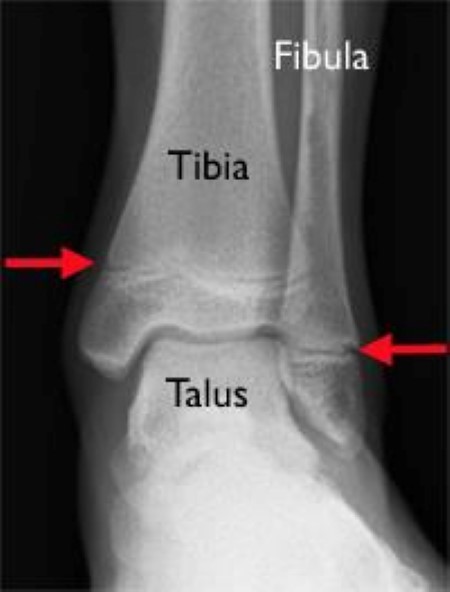

Tillaux fracture

In this Tillaux fracture, the blue arrow shows a widening of the growth plate, and the red arrow shows the fracture extending through the epiphysis and into the joint.